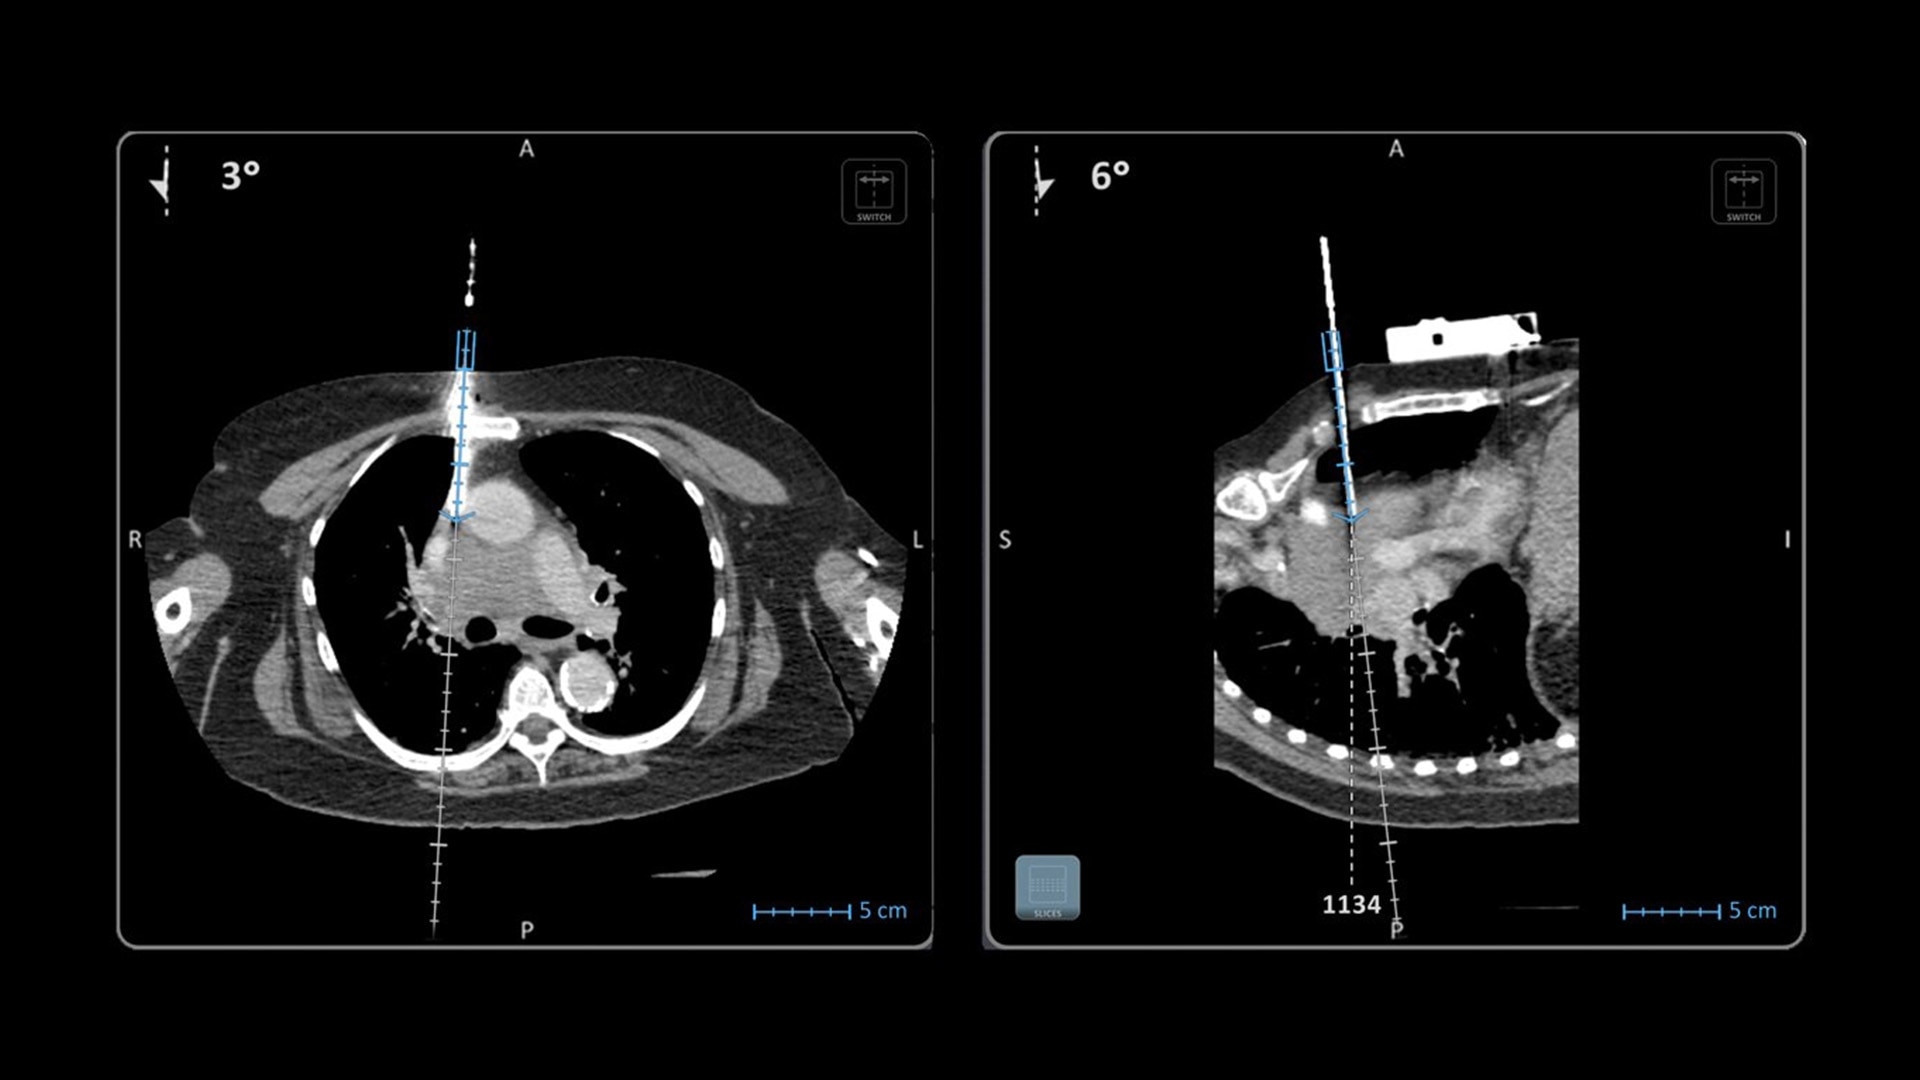

In interventional radiology, the success of the percutaneous procedure depends on correct needle positioning. The Imactis system helps the radiologist place one or more needles with great accuracy, in less time and with fewer control scans.

With real-time image reconstruction, live interactive navigation and no limit in angulation, the optimal clinical choices are clear.

Live 3D needle tracking, precise reproduction of your planned trajectory and continuous needle depth measurement help ensure optimal needle placement.